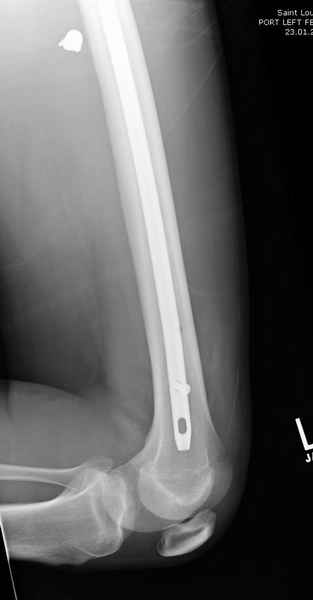

Учитывая, что больной получил травму не во время визита в церковь, и он является одним из представителем 40 миллионного “outstanding itizen”, без медицинской страховки, без работы в свои 39 лет, и без надлежающей ортопедической дисциплины у которого отсутсвует страх стрессового перелома, было рекомендовано оперативное лечение: профилактическое антеградное интрамедуллярное штифтование.

Выглядит агрессивно, и обычно госпиталь, беря финансовые расходы, остается в убытке, но мы всё же посчитали, что издержки от штифтования намного меньше, чем возможные финансовые и моральные издержки лечения таких больных, но с осложнением.

Методика штифтования при отсутствии большой зоны перелома как при онкологических профилактических штифтованиях, расверливание интрамедуллярного канала проводим с предварительным наложением дополнительного дренажного отверстия в дистальном отделе бедра (в данном случаи в канале оставили 6.5 мм канюлированный шуруп), иначе при создании давления в канале во время сверления имеется опасность эмболизации легочной артерии тромбом.